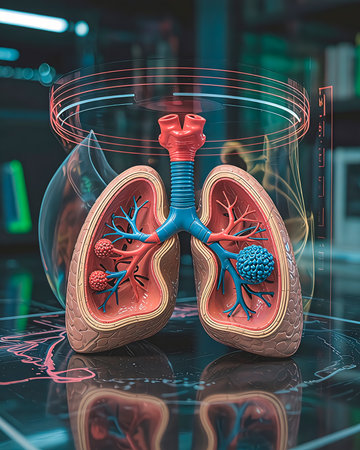

Anatomical model of human lungs featuring vivid colors and intricate patterns, highlighting the complexity of the respiratory system in an educational display.

A close up of a human lung with red, blue and pink veins. The lung is shown in a 3D model, with the red veins representing the blood vessels that supply oxygen to the lung tissue

Detailed 3D-printed lung model on black surface. Intricate bronchial trees, alveoli, red/blue arteries/veins. Cross-section shows pleural structures. Angled lighting, soft shadows. Blurred background: robotic arm, holographic airflow. Futuristic research lab. Anatomical precision.